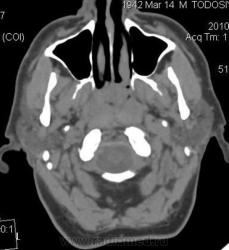

Мужчина 67 лет, обратился к отоларингологу с жалобами на заложенность носа, сосудосуживающие капли - без эффекта. Болен около месяца. На осмотре ЛОР-врач выявил образование свода носоглотки, направил на КТ.

Плотность 37-45 ед.Н, размеры 2х2х2.5 см. Бугристый контур, прилежит к нижнему контуру основной кости с ее деструкцией и прорастанием в основную пазуху. Диагноз не вызвал сомнений, решено контрастирование не выполнять. Направлен в областной онкодиспансер, ждем заключения.

Первые три - первичные аксиальные срезы в "мягкотканном" и "костном" окне в зоне интереса.